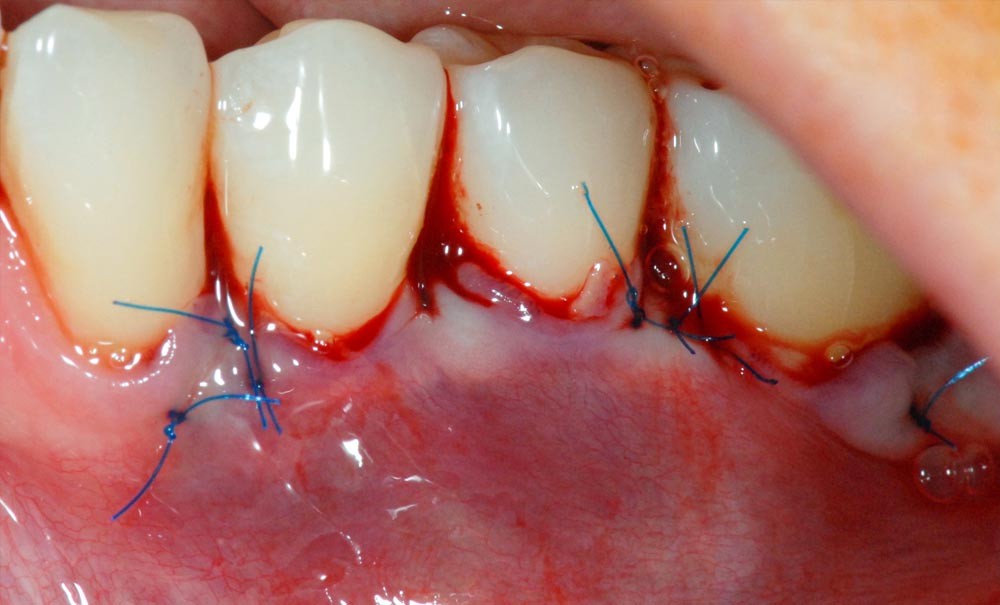

► Il était une fois une amie, médecin, qui présentait des récessions gingivales de 34 à 36. La sensibilité thermique de ces récessions indiquait un recouvrement par une technique de chirurgie plastique parodontale (fig. 1 et 2).

Face aux récessions de classe 1 de Cairo [1] et en présence d’un vestibule relativement profond, une technique de recouvrement radiculaire par lambeau positionné coronairement selon Zucchelli et De Sanctis [2] associé à un greffon conjonctif est choisie.

Cette technique permet de recouvrir des récessions gingivales contiguës par une traction coronaire après une dissection partielle superficielle au-delà de la ligne muco-gingivale. Grâce à un jeu d’incisions des papilles, les incisions de décharge ne sont pas nécessaires. Un greffon conjonctif prélevé au palais selon la technique de l’enveloppe [3] est placé sur les récessions et suturé en même temps que le lambeau par des points suspendus [4].

Dans notre cas clinique, l’intervention a duré un peu moins d’une heure.